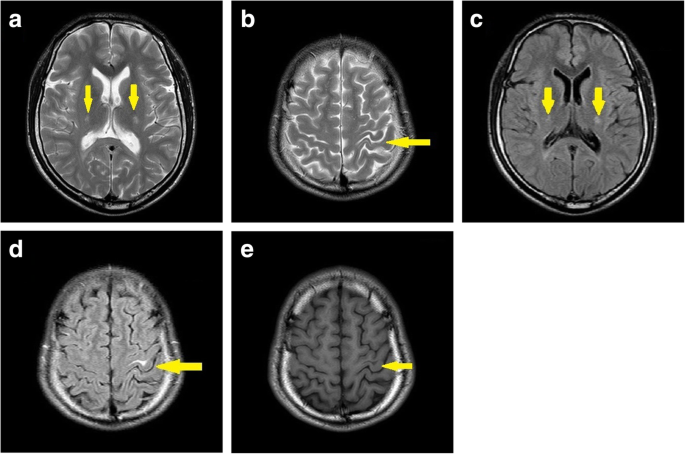

Brain MRI revealed a high-intensity signal in the left central gyrus cortex by fluid-attenuated inversion recovery (FLAIR) as well as T2-weighted images, while a decreased signal in the T1-weighted images and high-intensity lesions in the bilateral corticospinal tracts were detected (Fig. 3). Cervical spine and thoracic spine MRI showed mild atrophy of the spinal cord (Fig. 4). Moreover, electromyography indicated peripheral nerve demyelination, and both visual evoked potentials (VEP) and brainstem auditory evoked potential (BAEP) were normal.

In the Patient 1, electromyography indicated peripheral nerve demyelination, while brain MRI showed an increased signal intensity in the white matter encompassing the bilateral corticospinal tracts. The GALC enzymatic activity in leukocytes was 3.9 nmol/mg/17 h. In the Patient 2, the GALC enzymatic activity revealed 4.4 nmol/mg/17 h. These low activities proposed the diagnosis of Krabbe disease in both patients.